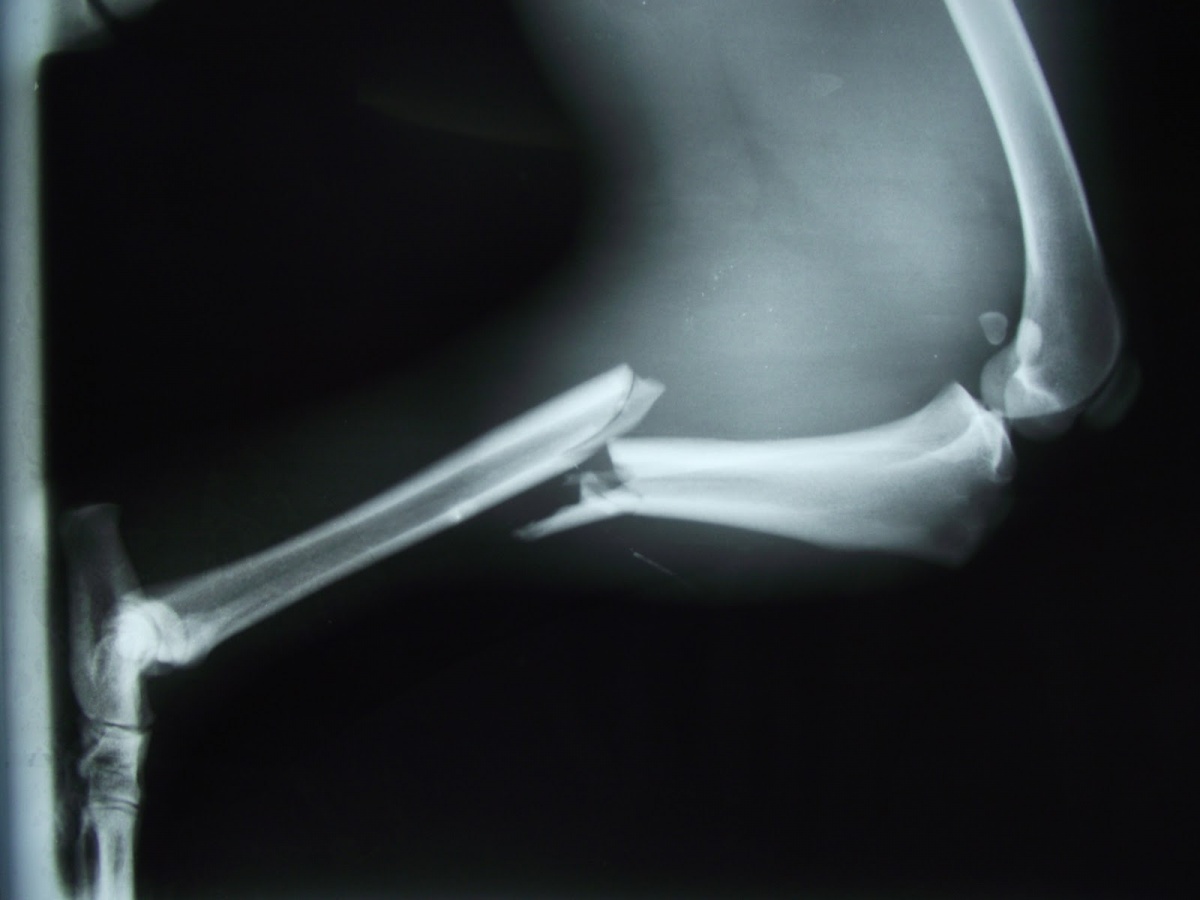

Vastag gipsz helyett 3D-s technológiával rögzíthetik a töréseket egy magyar informatikus ötletének köszönhetően, aki finanszírozót keres a megvalósításhoz – írta csütörtökön a Népszabadság.

Molnár Miklós a napilap cikke szerint egy szoftver segítségével 12 óra alatt nyomtatta kis a csuklójára megfelelő szorítót. A projektben az új rögzítés tesztelésére a fővárosi baleseti központ mellett a kecskeméti megyei kórház és a szegedi egyetem traumatológiája is részt venne. A programhoz az uniós kutatás-fejlesztési pályázaton szeretnének pénzt nyerni.

Az előzetes számítások szerint egy kisebb 3D-s csuklórögzítő ára 10 ezer, egy nagyobb, bokarögzítő 15-20 ezer forintba kerülhet. Tóth Ferenc, a Péterfy Sándor utcai Kórház rendelőintézet és Baleseti Központ igazgatóhelyettes főorvosa, aki Molnár Miklóssal együtt dolgozik a projekten a Népszabadságnak azt mondta, a végtagszkennelés után néhány óra alatt elkészíthető az eszköz, amelyet akár hónapokig is lehet viselni. Súlya mindössze 50 gramm, de masszívabb és tartósabb, mint a most használt gipsz.